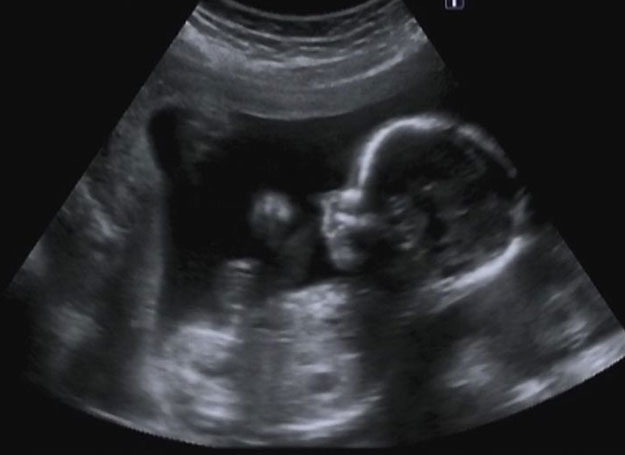

Spontaniczne poronienie obserwuje się w przypadku 10 do 20% rozpoznanych ciąż. Na łamach Rheumatology ukazały się wyniki duńskiego badania kohortowego, w którym oceniano wpływ reumatoidalnego zapalenia stawów (RZS) na ryzyko poronienia.

W pracy wykorzystano dane dotyczące ciąż z lat 1977 do 2014. W sumie zidentyfikowano ponad 2,6 mln ciąż. W przypadku kobiet poniżej 35 roku życia z historią RZS poniżej 5 lat odnotowano zwiększone ryzyko poronienia w porównaniu z kobietami w tej samej grupie wiekowej bez choroby (OR=1,25; 95% CI: 1,07-1,48). Podobnie, kobiety w tym samym przedziale wiekowym z historią choroby powyżej 5 lat miały zwiększone ryzyko poronienia w porównaniu z grupą kontrolną (OR=1,14; 95% CI: 0,96-1,34). W przypadku kobiet powyżej 35 roku życia z RZS ryzyko poronień nie różniło się istotnie w porównaniu z populacją ogólną niezależnie od czasu trwania RZS.

Na podstawie opisywanego badania wydaje się, że RZS wpływa na ryzyko poronień głównie u kobiet poniżej 35 roku życia w porównaniu z populacją ogólną ciężarnych. Po 35 roku życia choroba nie ma tak silnego wpływu na ryzyko poronienia, chociaż samo ryzyko wzrasta wraz z wiekiem.